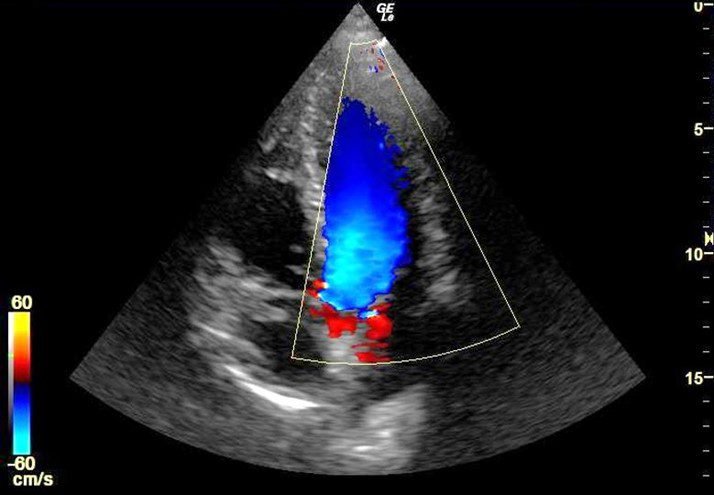

Colour Doppler is a specialized ultrasound technique used to visualize and evaluate blood flow in real time. It helps doctors assess the direction, speed, and quality of blood flow in arteries and veins throughout the body. In pregnancy, Colour Doppler plays a crucial role in monitoring blood circulation between the mother and baby, checking for conditions like restricted blood flow or complications in the placenta and umbilical cord. Outside of pregnancy, it is used to detect vascular disorders, blood clots, varicose veins, and heart-related issues. The scan is non-invasive, painless, and provides critical information that cannot be seen through regular ultrasound. At Jantasarvajanik Hospital, we use advanced Colour Doppler technology to deliver accurate and timely diagnostics that support effective treatment planning. Our expert radiology team ensures patient comfort and precision in every scan, helping you take proactive steps toward better health.